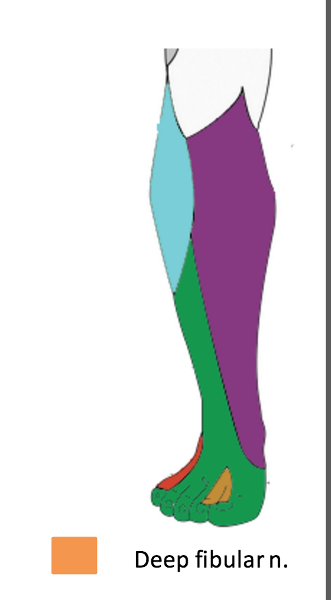

The deep fibular nerve is the (medial/lateral) division of the _________-

medial; common fibular nerve

What is the path of the deep fibular nerve?

travels between tibialis anterior and extensor hallucis longus

continues onto the dorsum of the foot for sensory innervation in the flip flop area

What is the pathway of the superficial fibular nerve?

OCD of deep fibular nerve

O common fibular nerve

C arises between fibularis longus and neck of fibula; passes through extensor digitorum longus and descends on interosseous membrane. crosses distal end of tibia and enters dorsum of foot.

D tibialis anterior, extensors digitorum brevis and longus, extensor hallucis brevis and longus, and fibularis tertius. lateral cutaneous of big toes, medial cutaneous of second toe.